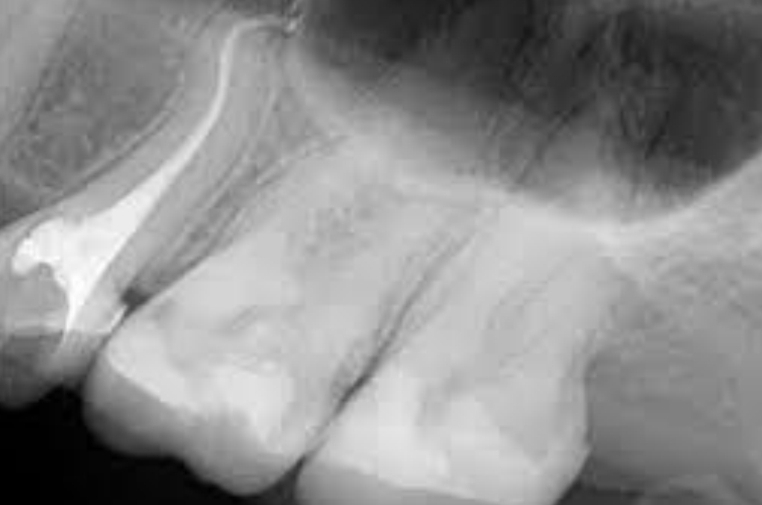

What are dilacerations?

Sharp bend in root - from trauma or bony interference during root formtation

Dilacerations

Apical curvature in root (disto-palatal direction). In lateral incisor.

Files straigten canal and leave apical 3rd uninstrumented